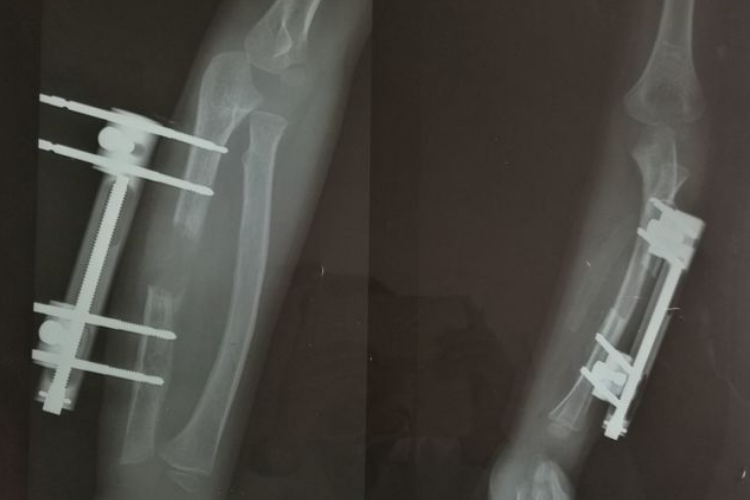

骨痂是骨延长愈合过程中新形成的连接骨折两端的骨组织,骨延长骨痂生长过程中先形成纤维骨痂再形成骨性骨痂。

纤维骨痂形成后,成骨细胞活跃,分泌出均质透明的类骨基质,继之形成类骨组织,而后钙质在类骨基质间不断沉积形成骨组织,此时骨痂称为骨性骨痂。

骨延长术后长骨痂时,应注意营养的补充,以增加骨中钙和磷的吸收,促进骨痂修复。在日常生活中患者要注意补充含钙的食物。